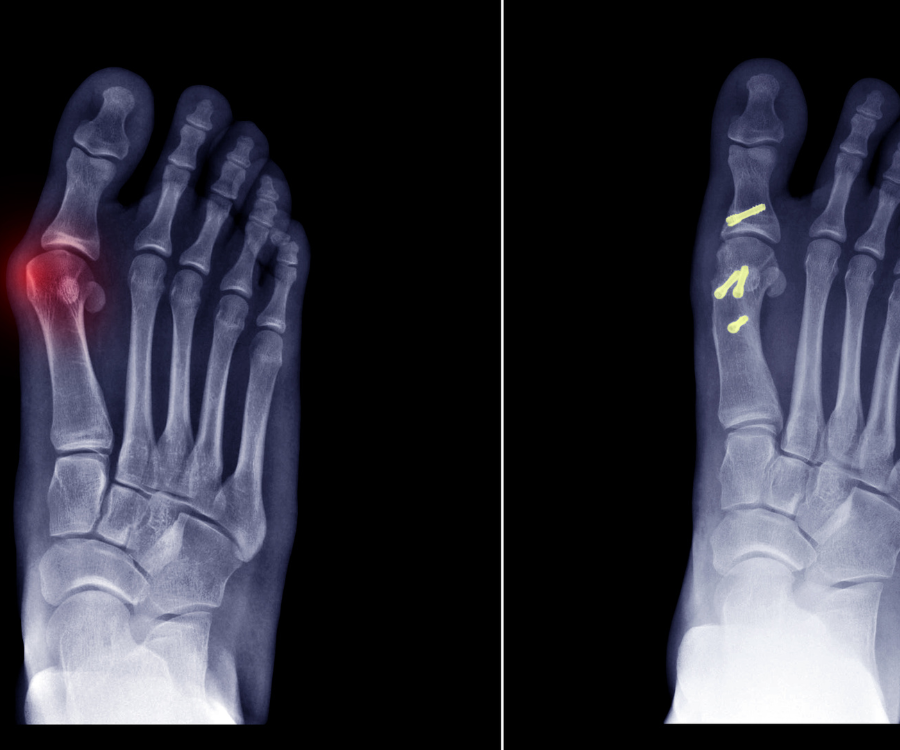

Bunion surgery can be performed using various techniques, depending on the severity of the bunion and your surgeon’s preference. Common procedures include:

- Lapidus Procedure: This involves fusing the joint between the big toe and the first metatarsal bone.

- Chevron Osteotomy: This procedure involves cutting and realigning the first metatarsal bone to correct the angle of the big toe.

- Excision of the Bunion: In some cases, the surgeon may simply remove the bony bump of the bunion.